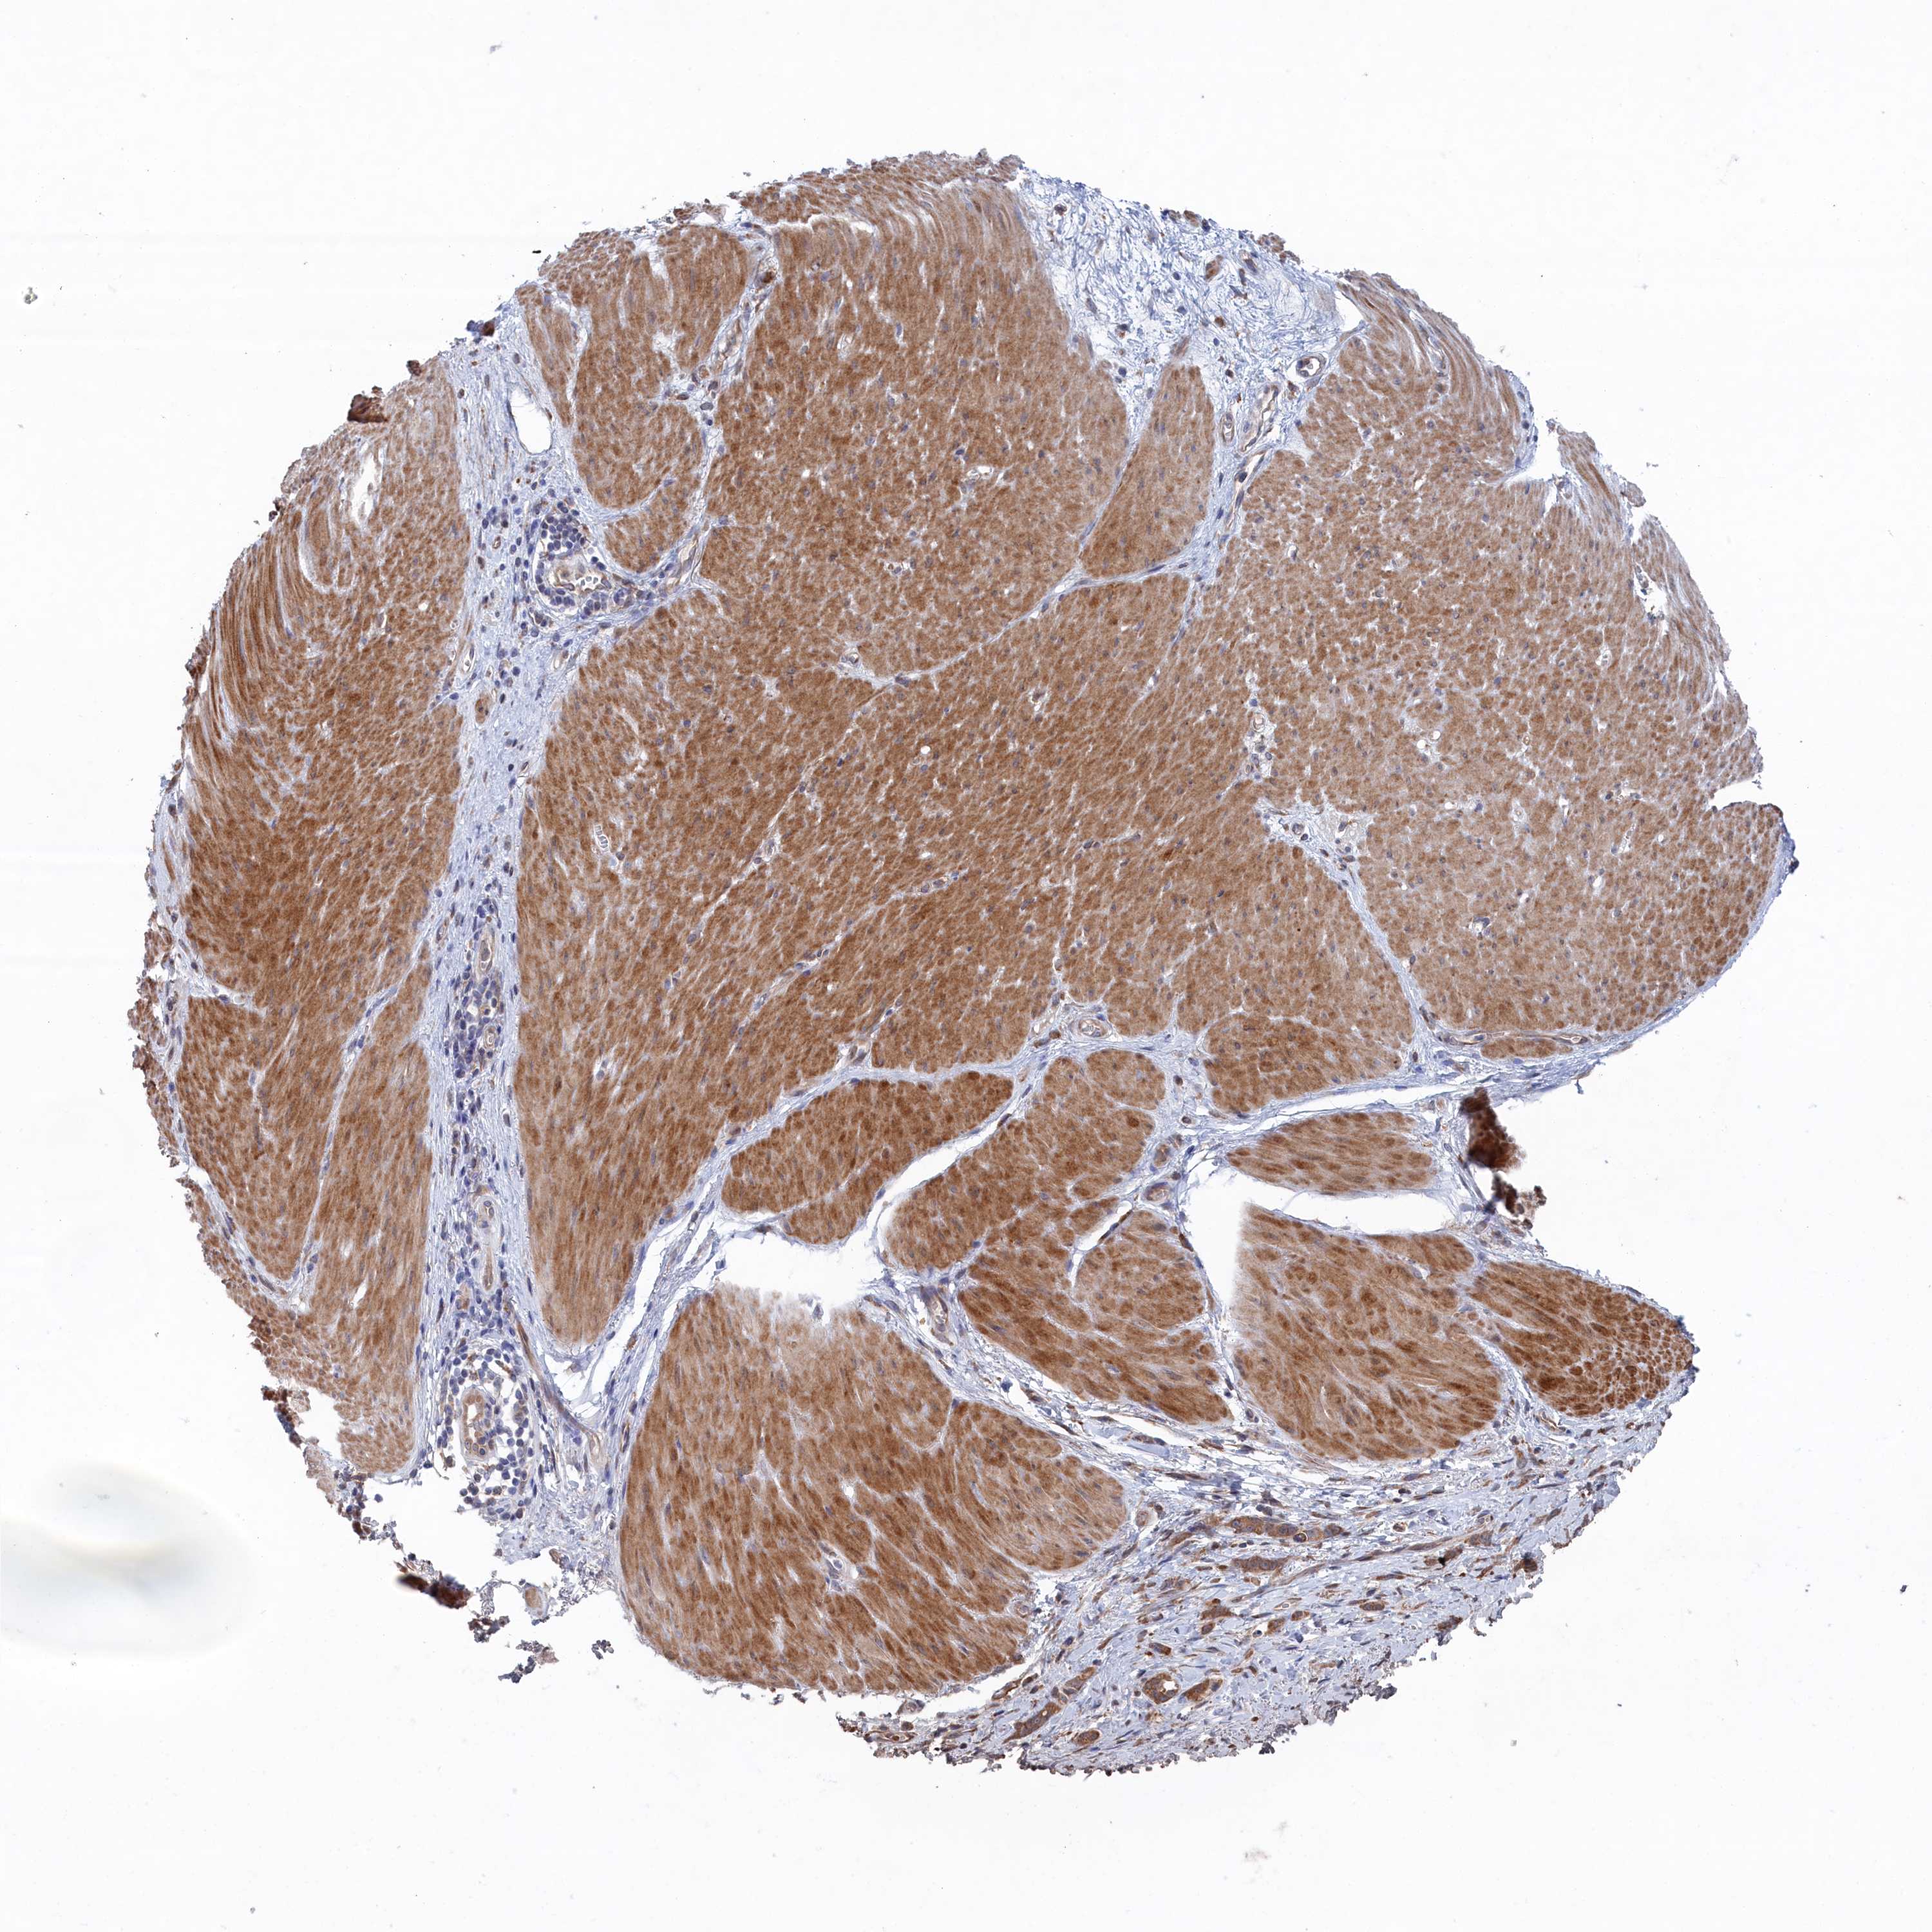

STOMACH CANCER - Protein expressioni

A mouse-over function shows sample information and annotation data. Click on an image to view it in a full screen mode. Samples can be filtered based on level of antibody staining by selecting one or several of the following categories: high, medium, low and not detected. The assay and annotation is described here.

Note that samples used for immunohistochemistry by the Human Protein Atlas do not correspond to samples in the TCGA dataset.

Antibody stainingi

Antibody staining in the annotated cell types in the current human tissue is reported as not detected, low, medium, or high, based on conventional immunohistochemistry profiling in selected tissues. This score is based on the combination of the staining intensity and fraction of stained cells.

Each image is clickable and will lead to virtual microscopy that enables deeper exploration of all samples and also displays staining intensity scores, fraction scores and subcellular localization as well as patient and tissue information for each sample.

Antibody HPA043057

Staining

High

Medium

Low

Not detected

Intensity

Strong

Moderate

Weak

Negative

Quantity

>75%

75%-25%

<25%

None

Location

Nuclear

Cytoplasmic/membranous

Cytoplasmic/membranous,nuclear

Adenocarcinoma, NOS